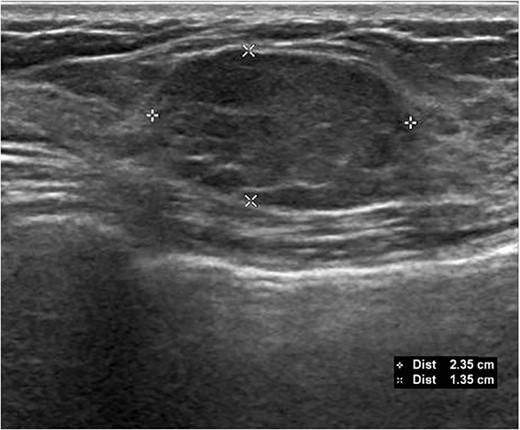

A 26-year-old female presented with a longstanding palpable fibroadenoma in the left breast. She was first investigated with ultrasound imaging showing a lobulated 2.4 × 2.5 × 1.4 cm hypoechoic lesion with well-defined margins (Fig. 1). She underwent core needle biopsy of the lesion which was histologically proven to be a fibroadenoma. There was no evidence of malignancy. She was later discharged and presented 6 years later with a history of recent enlargement of the left breast lump. Ultrasound imaging now showed increase in the size of the left breast fibroadenoma to 3.2 × 2.7 × 1.6 cm and development of an irregular outline (Fig. 2). Because of increasing size of the lesion and new indeterminate features, excision biopsy was advised. Post-excision histology revealed a 5-mm focus of classic lobular carcinoma in situ (LCIS) with a 0.6-mm area of microinvasive carcinoma within the fibroadenoma (Figs 3–6). The carcinoma was estrogen and progesterone receptor positive and Her2 negative. Atypical ductal hyperplasia was seen in the breast tissue adjoining the fibroadenoma. After presentation at our multidisciplinary tumor board, sentinel lymph node biopsy for staging of the invasive carcinoma, radiotherapy and endocrine therapy for risk and recurrence reduction, as well as genetic testing in view of her young age was discussed with the patient. Because of the small size of the invasive carcinoma, potential cost and morbidity associated with sentinel lymph node biopsy, no further surgery was performed. The patient was agreeable to proceed with radiotherapy and endocrine therapy but requested to defer genetic testing.

Initial ultrasound demonstrating the left breast mass measuring 2.4 × 2.5 × 1.4 cm. Core needle biopsy of this mass showed benign fibroadenoma with no malignancy.